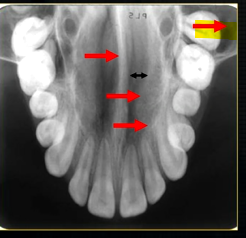

dental radiographic images are 2D representations of the 3D teeth and bones of the skull

resultant radiographs are always 2d demonstrations of a 3d object - all structures, internal and external will be superimposed on one another

how the anatomy is presented geometrically is dependent on the relative positions of the patient, image receptor and the X ray beam

occlusal view shows how maxillary air sinus varies in size

density of the maxillary sinus varies

blacker in some parts than in others

shape varies and the density of the overlying bone varies